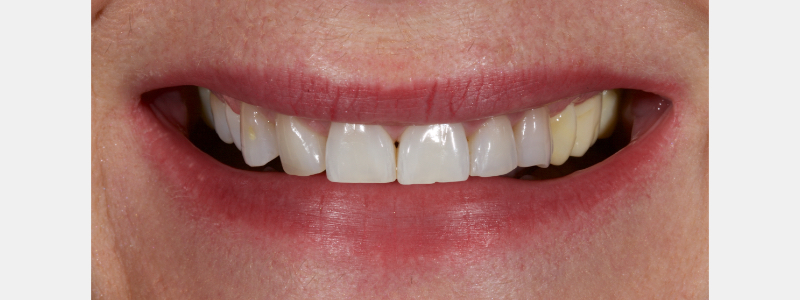

To illustrate this protocol, we will explore the case of a 55-year-old female patient — a dentist — with esthetic and functional concerns as well as moderate to advanced tooth surface loss (TSL).

The anterior teeth had lost around 25% of the coronal structure, and dentin was exposed (Figs. 1–3). The patient requested a minimally invasive solution.